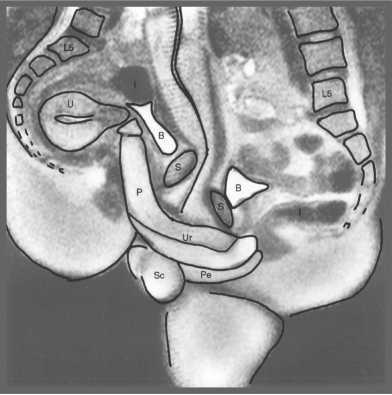

![]() Рис. 5. «Соитие». Рисунок из дневников Леонардо да Винчи (1475–1518 гг.) В одном из рисунков, содержащихся в известных «Дневниках» Леонардо, — «Фигура соития» — изображен срез гениталий мужчины и женщины во время полового акта стоя. Рисунок отражает его понимание, что член входит во влагалище, как ключ в замочную скважину. Он писал: «Женщине нравится, чтобы пенис был как можно крупнее, тогда как мужчина желает от женского чрева обратного». Недавние рентгенологические исследования с трехмерной реконструкцией изображения позволили уточнить анатомические соотношения гениталий в процессе полового акта; эти данные во многом подтвердили представления Леонардо до Винчи. Статья «Магнитно-резонансное изображение мужских и женских гениталий в процессе соития»11 получила в 2000 году Шнобелевскую (антинобелевскую) премию, что свидетельствует как минимум о проявлении интереса к данному исследованию. ![]() Рис. 5 а. МРТ гениталий в процессе полового акта. В период, когда Леонардо занимался изучением строения человеческого тела, в средневековой Европе господствовали медицинские взгляды греческого ученого Галена (131–217). Он считал, что всем человеческим телом управляет «внутреннее тепло» (воздух). Оно же поступает в пенис и вызывает эрекцию. Еще до систематических анатомических исследований, начавшихся с 1503 года, Леонардо присутствовал на публичной казни через повешение и затем вскрытии трупов этих преступников. Он пишет: «Я видел мертвецов с эрегированным членом, что часто происходит у тех, кого казнят повешением. Их пенисы были очень плотны и тверды и наполнены большим количеством крови». Догадка о возникновении эрекции в результате интенсивного притока крови была подтверждена Леонардо да Винчи дальнейшими исследованиями. Амбруаз Паре, которого считают отцом современной хирургии, опубликовал в 1585 году научную работу, содержащую аналогичный вывод. Вероятно, ему не было известно, что на 100 лет раньше это открытие сделал не медик, а великий художник. Однажды бельгийский врач Андреас Везалий (1514–1564), прогуливаясь ночью за городской стеной, набрел на труп повешенного преступника и отрезал у него руку и половой член. Исследовав их, он сделал ошеломляющий вывод: многое из написанного Галеном о теле человека не соответствует действительности. В 1543 году Везалий опубликовал свой труд «О строении человеческого тела» объемом 663 страницы (28 см в ширину, 42 в высоту, в переплете из пурпурного бархата). Как писал Везалий: «В отношении полового члена истина заключается в том, что при акте зачатия этому органу дана такая сила наслаждения, что и молодые, и старые мужчины ощущают потребность размножаться». Анатом и физиолог голландского происхождения Ренье де Грааф завершил к 1668 году самое детальное на тот период исследование строения полового члена. Он использовал свою методику достижения стойкой эрекции членов трупов и значительно превзошел предшественников в понимании ее механизмов. Им доказана не только важная роль интенсивного притока крови к пенису, но и ее стойкого удержания. Гипотеза, что это происходит за счет сжатия мышц, окружающих кавернозные тела, оказалась неверной. Вскоре после опубликования своего труда «Трактат относительно генеративных органов мужчины» он в 1673 году умер, занимаясь лечением больных чумой. Ему было 32 года… Еще один шаг к пониманию строения и функционирования полового члена сделал голландец Фредерик Рюйш (1638–1731). Используя специальный состав жидкости и шприцы, он изготавливал препараты частей тела, словно отлитые из воска. При этом в пенисе были четко различимы артерии и вены. Его модели органов не только были объектом изучения, но также составили коллекции, в которых основными экспонатами служили половые члены. Они были раскуплены европейскими монархами, включая царя Петра I. ![]() Рис. 6а. Кавернозная ткань во время расслабления пениса. ![]() Рис. 6б. Кавернозная ткань во время эрекции пениса. Чтобы закрасить оставшиеся белые пятна в истории познания строения и эрекции полового члена, опишем последние крупнейшие открытия в этой области. В самом начале XXI столетия к урологам пришло понимание, что именно за счет расслабления гладкой мускулатуры, которая входит в состав мельчайших артерий (артериол) и ячеек (синусоидов), кавернозная ткань способна принять и удерживать достаточное количество крови для создания ригидности (твердости) полового члена. При быстром расслаблении этой гладкой мускулатуры артериолы расширяются, сопротивление поступающему потоку крови резко падает, а увеличившаяся в объеме кавернозная ткань прижимает к белочной оболочке и сдавливает вены, по которым кровь могла бы утекать (окклюзия вен). Притекающая кровь оказывается как бы в ловушке, давление в кавернозных телах резко нарастает и становится выше артериального систолического. Однако трофика (питание) тканей члена не нарушается, так как минимальный уровень притока и оттока крови сохраняется. Эти предварительные сведения и выводы были подтверждены последующим изучением анатомии пениса с использованием сканирующей электронной микроскопии. Оставалось неясным, что представляет собой вещество, вызывающее расслабление гладкой мускулатуры кавернозной ткани и расширение ее сосудов и синусоидов. Эту загадку независимо друг от друга разгадали трое ученых: Роберт Фарчготт, Луис Игнарро и Ферид Мурад. Им удалось доказать, что молекула оксида азота (NO), вырабатываемая эндотелием сосудов, и является тем самым веществом, которое вызывает расширение всех периферических (мельчайших) артерий. Основные научные исследования относятся к 1992 году. Позднее авторы стали лауреатами Нобелевской премии (1998) за работу «Монооксид азота как сигнальная молекула в сердечно-сосудистой системе». Все сосудистые реакции, осуществляющие эрекцию, контролируются нервной системой. Ее активное участие в этом процессе впервые установил в 1863 году немецкий ученый Конрад Экхард. Он обнаружил напряжение члена собаки при воздействии на тазовые нервы электрическим током. |